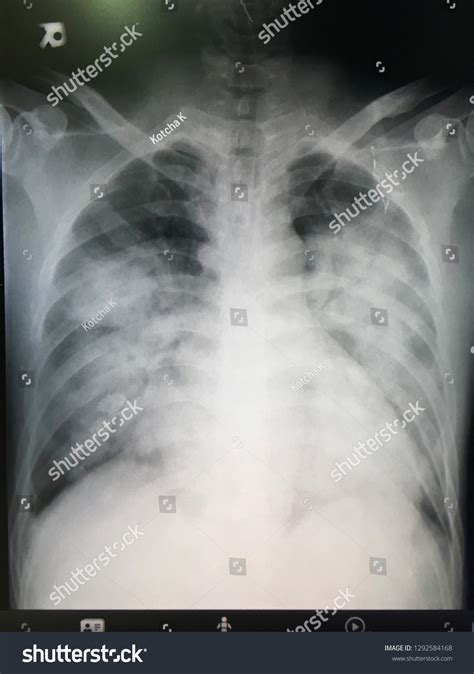

ARDS is a complex syndrome that can be triggered by various factors, including sepsis, pneumonia, trauma, and aspiration. It is marked by the rapid onset of bilateral pulmonary infiltrates, refractory hypoxemia, and decreased lung compliance. The Ards Chest X Ray is instrumental in visualizing these pulmonary infiltrates, which appear as diffuse, bilateral opacities on the radiograph.

The Ards Chest X Ray is often the first imaging modality used to evaluate patients suspected of having ARDS. It provides a quick and relatively inexpensive way to assess the lungs for signs of inflammation and edema. Key findings on an Ards Chest X Ray include:

• Bilateral pulmonary infiltrates

• Diffuse opacities

• Air bronchograms (air-filled bronchi surrounded by consolidated lung tissue)

• Absence of pleural effusions or cardiomegaly

These findings, when combined with clinical criteria such as the PaO2/FiO2 ratio (the ratio of arterial oxygen partial pressure to fractional inspired oxygen), help confirm the diagnosis of ARDS.

• Bilateral Infiltrates: ARDS typically presents with bilateral, diffuse infiltrates that are often more pronounced in the dependent lung zones.

• Air Bronchograms: These are visible air-filled bronchi within consolidated lung tissue and are a hallmark of ARDS.

• Absence of Pleural Effusions: Unlike other causes of pulmonary edema, ARDS is usually not associated with significant pleural effusions.

• Cardiomegaly: The heart size is typically normal in ARDS, helping to differentiate it from cardiogenic pulmonary edema.